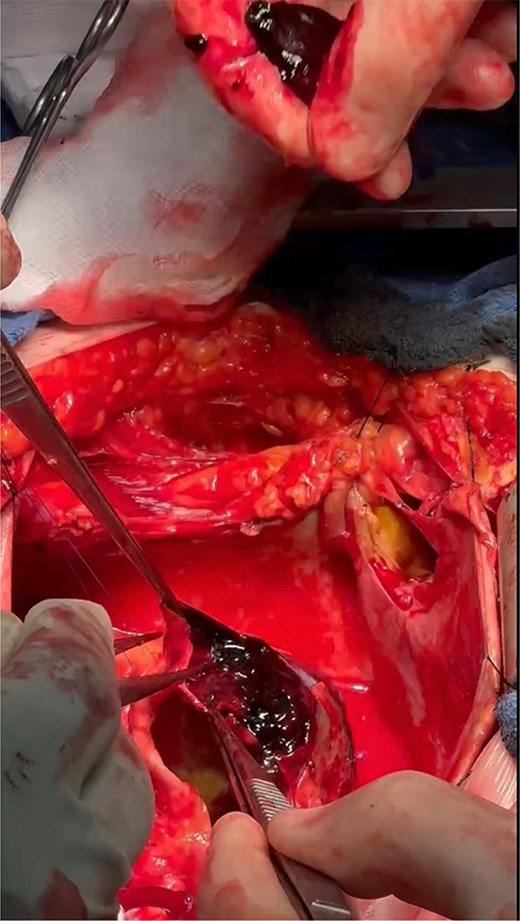

The operation was performed via median sternotomy, with the aneurysm immediately visible post sternotomy (Fig. 5). The pericardium was carefully opened without complication, and due to the right atrium being inaccessible, cardio-pulmonary bypass was established using central ascending aortic cannulation and femoral venous cannulation, with antegrade cardioplegia (Fig. 5). The giant CAA was then opened directly where it was uncovered that the aneurysm wall had also dissected, and was paper thin (Fig. 6). The thrombus was evacuated, perforating branches were identified and oversewn, of which there were two. Following this, an endoscopically harvested saphenous vein graft was used to directly, end-to-end anastomose the proximal and distal necks of the aneurysm, bypassing the sac entirely (Fig. 7). The patient was successfully weaned from Cardiopulmonary Bypass and the procedure concluded without complication.

Direct anastomosis of saphenous conduit to the distal neck of the aneurysm using an end-to-end technique.